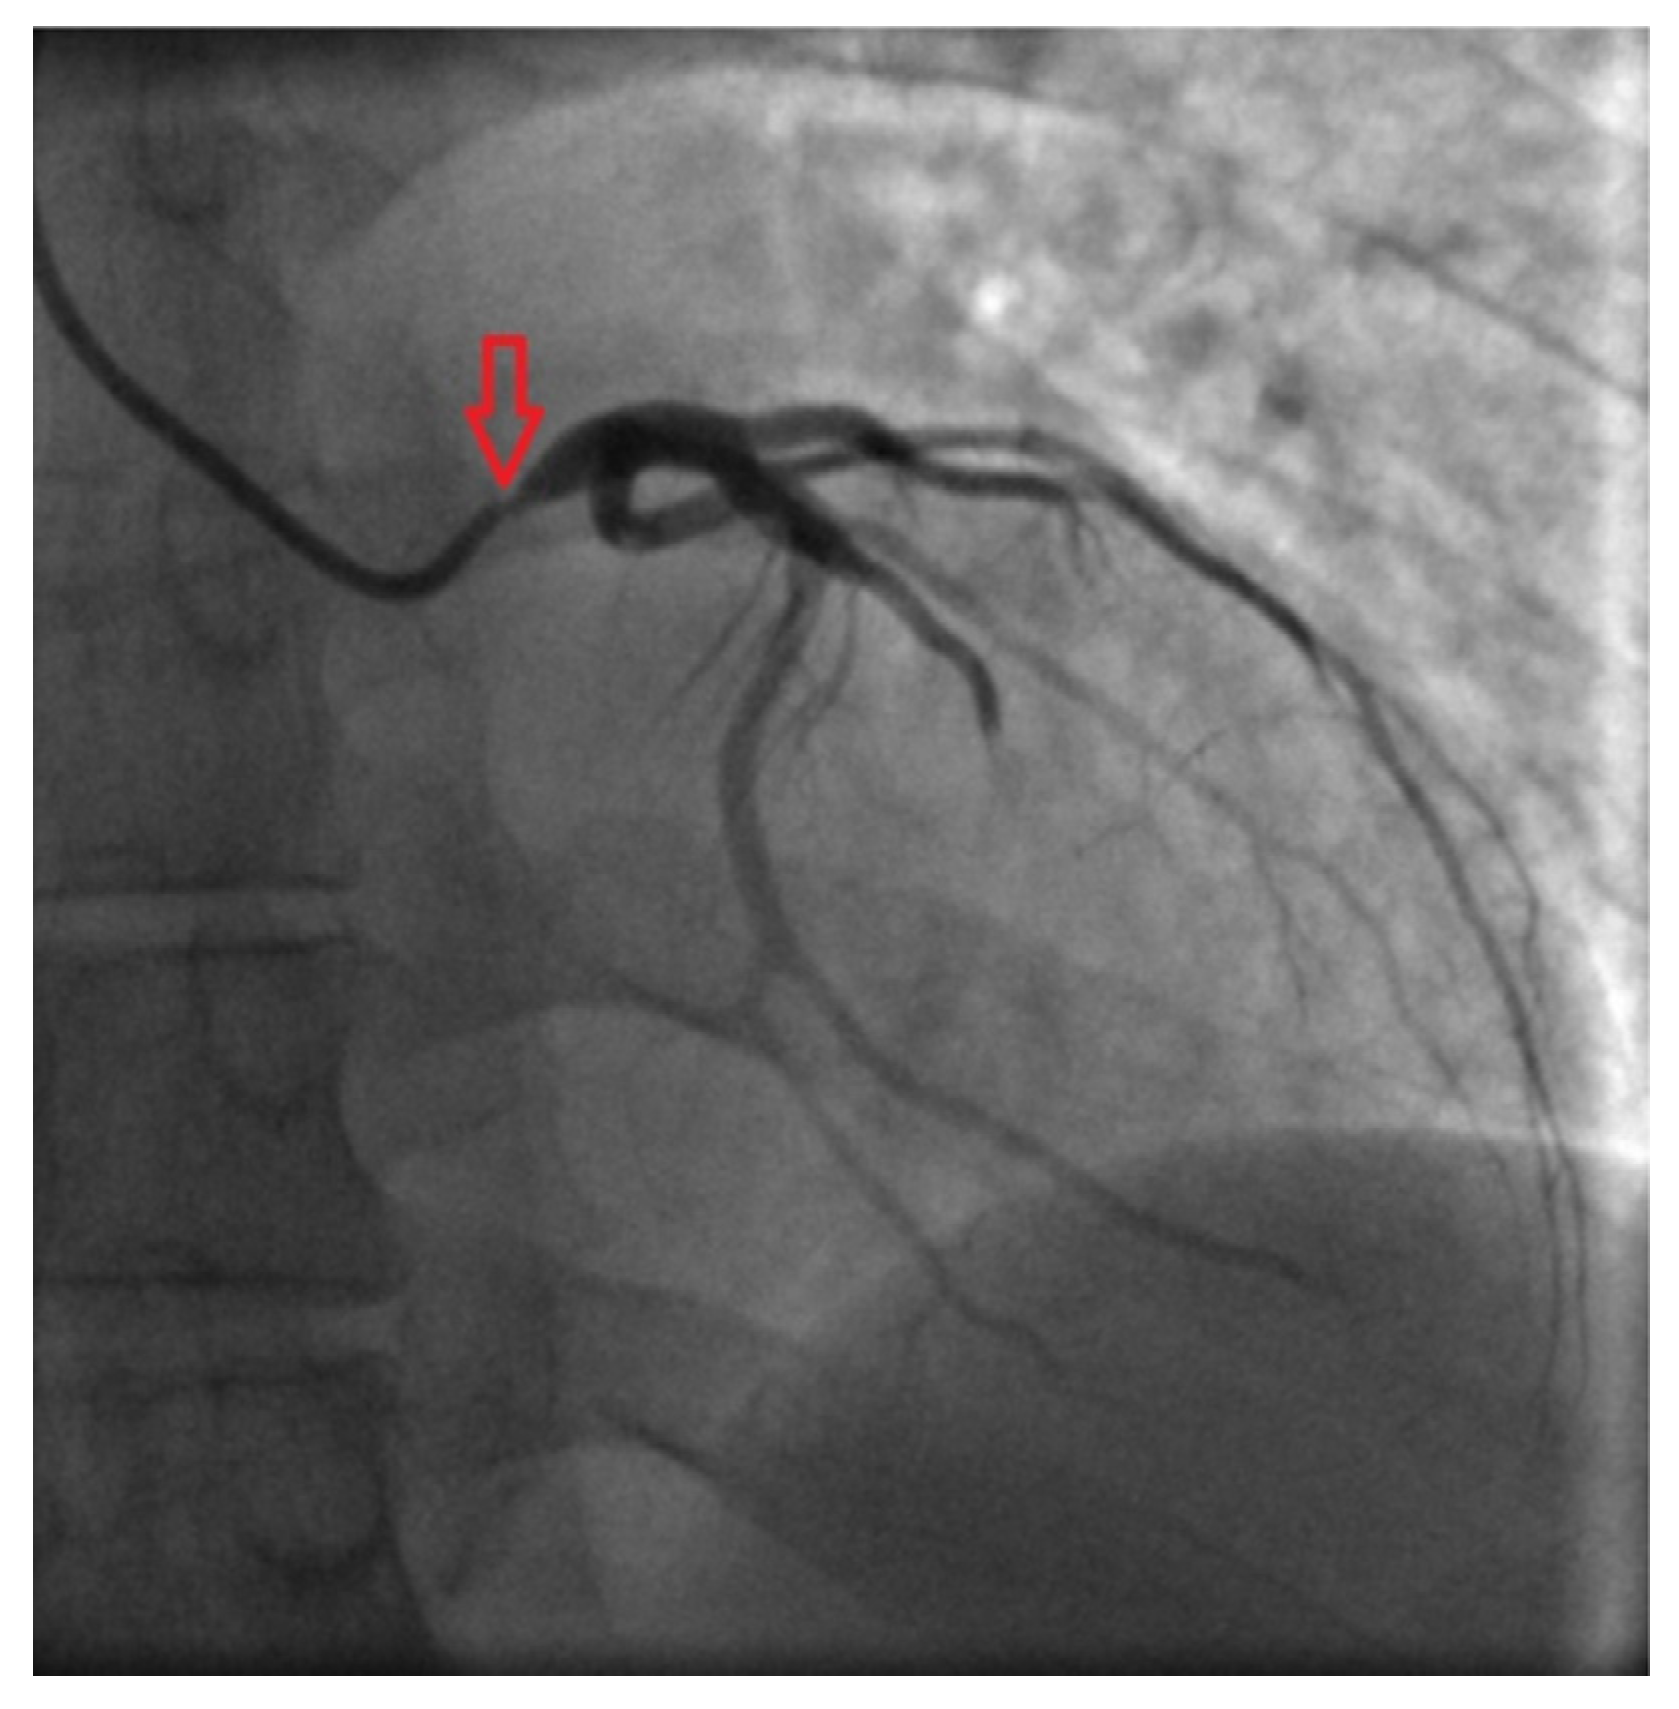

Coronary angiography clarified causes of chest pain: subocclusions of right and left main coronary arteries were found (Fig. 3 and Fig. 4).

Fig. 4. - Right coronary angiogram shows critical ostial stenosis.